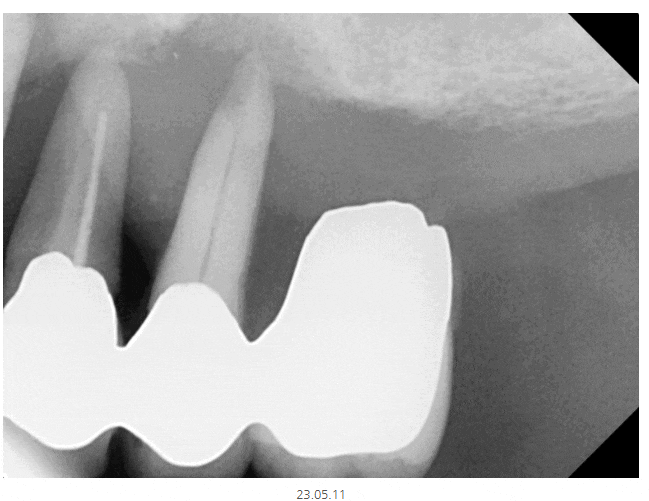

▼상한 치아 확인하기▼

힘이 누적해서 가해져서

잇몸 속의 뼈와 치아의 뿌리도 계속해서 손상되게 되는데요.

그래서 사진을 보시면 앞쪽 치아 뿌리가 드러났죠~?

잇몸뼈가 내려가서 그런건데

바로 손상되었다는 증겁니다!!!

x-ray 상에서 까맣게 보이는 부분이

뼈가 녹은 부분입니다.